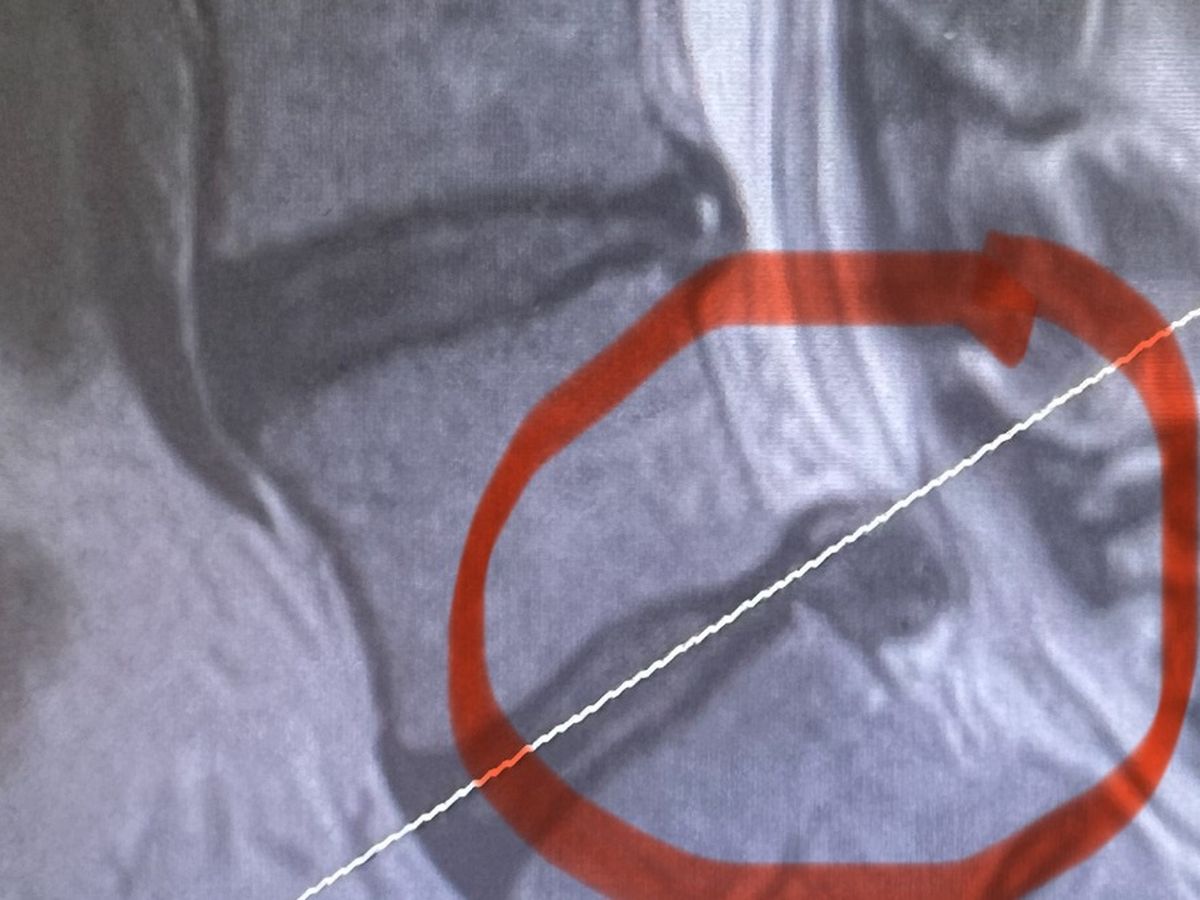

About a month ago I hurt my back. I have only missed one day of work and that was the day I went to the emergency room. I have 2 herniated discs one at L5 and one at S1. I have finally received a date for the surgery on January 25. This will be a full discectomy of my S1. Please pray before you give. I would rather pay you back the money then just ask you to donate so if that works please let me know. I also know this is the worst time to have money troubles. Thank you so much. I love all the well wishes and messages that everyone has sent me on Facebook.